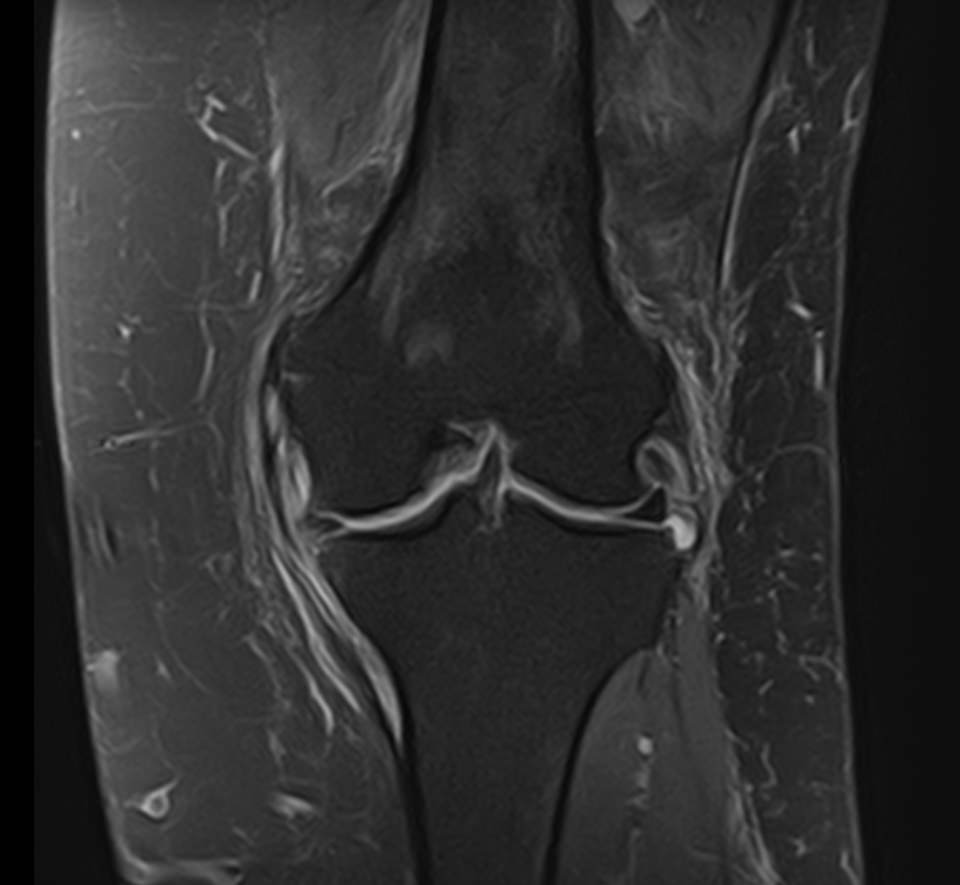

Магнитно-резонансная томография является высокоинформативным методом выявления причин возникновения заболеваний коленного сустава. В клинике «Доступная медицина» диагностика осуществляется на новейшем высокопольном томографе закрытого типа TOSHIBA VANTAGE TITAN 1,5 Тесла, обеспечивающем высочайшее качество изображений исследуемой зоны.

Томограф позволяет детально визуализировать как костные структуры колена, так и окружающие мягкие ткани данной анатомической области, включая мышцы, связки, нервные сплетение, сосуды.